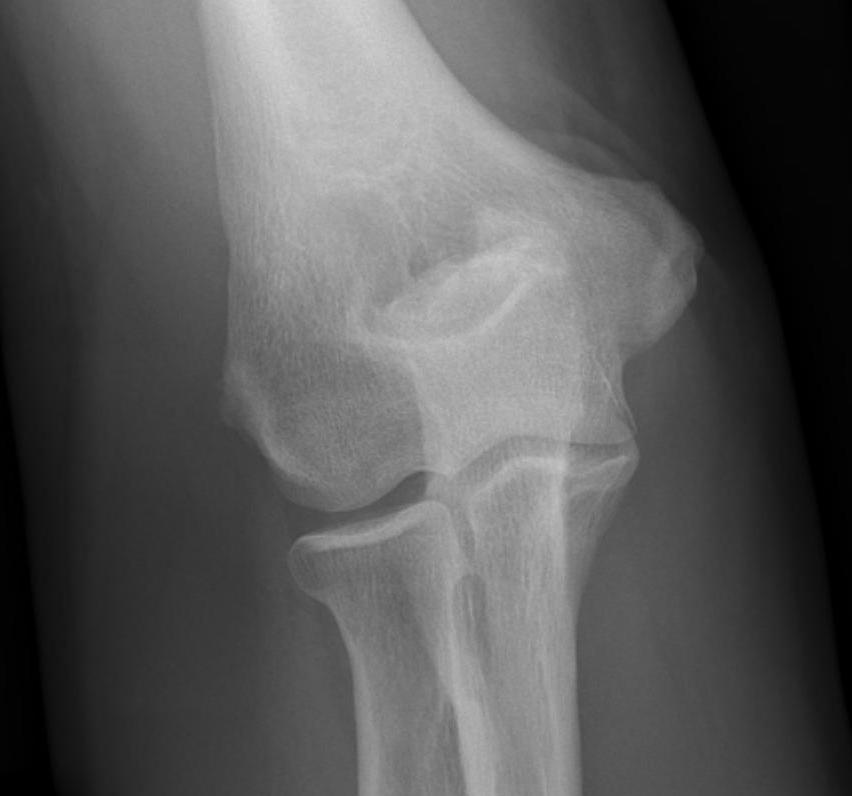

X-ray

Early stage

- preserved radiocapitellar and ulnohumeral joints

- osteophytes of the olecranon and coronoid

Lateral xray demonstrating olecranon and coranoid osteophytes